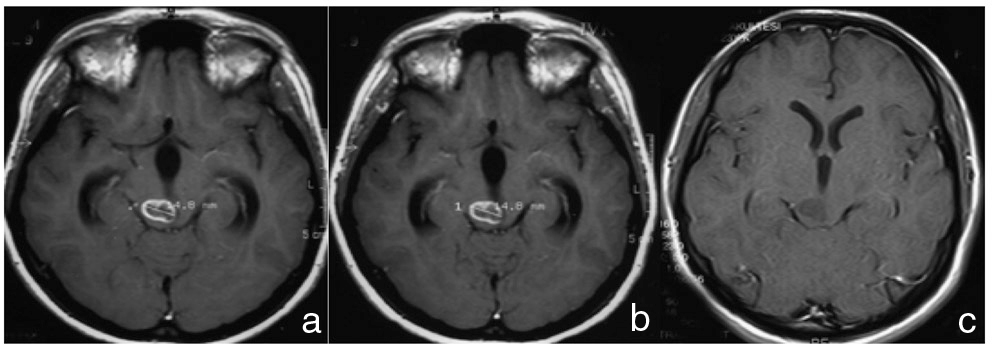

A 24-year-old Turkish woman experienced headaches 9 years ago and MR imaging performed in Turkey showed a mass of the brain stem with CE (Fig. 1a). Her symptom was relieved spontaneously. Scheduled MR imaging follow up was performed afterwards. During this follow-up period, the MR imaging showed spontaneous disappearance of CE without enlargement of the tumor (Fig. 1b, c). This woman, now living in Japan, was admitted to our hospital with headache and nausea in May 2011. During the previous week, she experienced paroxysmal headache and nausea several times a day. Physical examination, including a neurological examination, found no abnormalities. Computed tomography (CT) scan showed hydrocephalus and low density mass at midbrain (Fig. 2a). MR imaging performed at our hospital showed enlargement of midbrain lesion without CE together with severe stenosis or obstruction of aqueduct (Fig. 2b–f). With diagnosis of low grade glioma causing obstructive hydrocephalus, and with some possibility of demyelinating disease, inflammatory disease, or parasitic infectious disease, she underwent endoscopic third ventriculostomy (ETV) and tumor biopsy. Histology of the tumor biopsy revealed biphasic morphology; a neurocytic and an astrocytic component (Fig. 3a–d). The neurocytic component consisted of neurocytic rosettes and perivascular rosettes with positive staining for synaptophysin (SYN) and neurofilament protein (NFP). The astrocytic component intervened rosettes and was positive for glial fibrillary acidic protein (GFAP) and oligodendrocyte transcription factor 2 (Olig2). Ki-67 labeling index was low at 1.1%. An RGNT was diagnosed. Her post-operative course was uneventful, and size of ventricle diminished on postoperative CT scan. She has been followed for 17 months postoperatively without any clinical worsening or tumor enlargement.

Magnetic resonance (MR) imaging performed previously. Gadolinium-contrasted T1-weighted MR imaging at first time (a) showing hypointense mass with contrast enhancement of midbrain in 2002. Follow-up MR imaging 3 months later (b) showing no change. Follow-up MR imaging 9 months after first MR imaging (c) showing spontaneous disappearance of contrast enhancement without tumor growth.